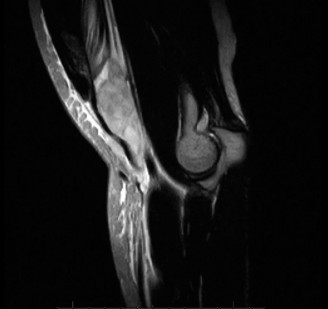

A 45-year-old carpenter presents with shoulder pain that has been ongoing for the last 3 months. He denies any significant injury. He describes night pain and significant discomfort at work. His imaging is shown in Figure 2–9. What is the most likely diagnosis?

Figure 2–9_From Shi LL, Mullen MG, Freehill MT, et al. Accuracy of Long Head of the Biceps Subluxation as a Predictor for Subscapularis Tears. _Arthroscopy 2015;32(4):615–619.

Discussion

The correct answer is (A). Medial subluxation of the biceps tendon as seen in this MRI is commonly associated with a tear of the subscapularis tendon which attaches to the lesser tuberosity. This patient’s pain may in part be attributable to the subscapular tear and this should be evaluated for during physical examination. Supraspinatus tears (Answer B) cannot be easily visualized on axial views and are not associated with medial biceps subluxations. A labral tear and ALPSA lesion (Answers C and D) are not seen on the images provided. The question stem and MRI are not suggestive of shoulder instability (Answer E). Objectives: Did you learn...? Diagnose and treat acute rotator cuff tears?